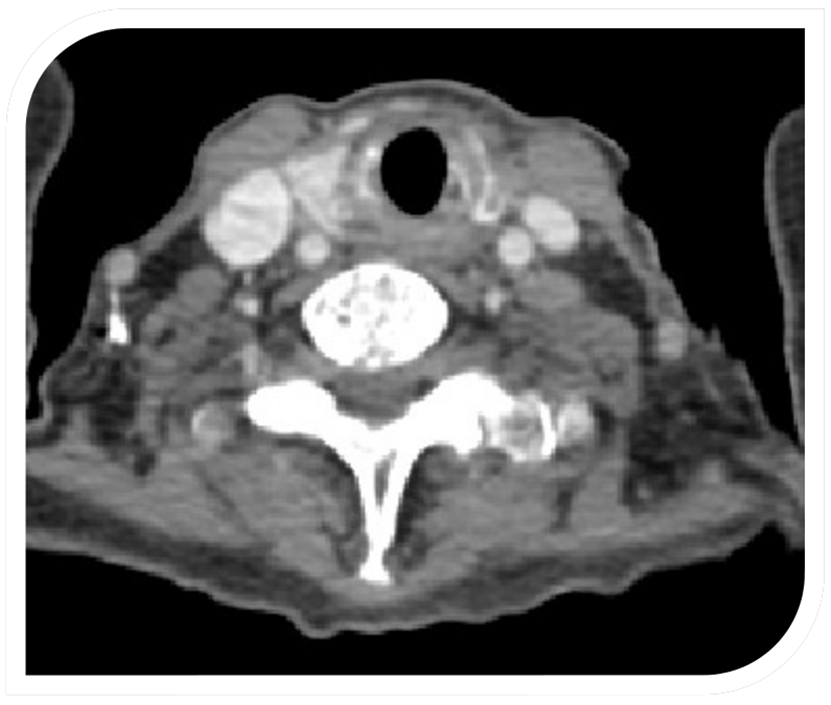

TAC contrastado de cuello. Nódulo tiroideo izquierdo de alto riesgo. Biopsia reporta: nódulo sólido tiroideo izquierdo, lesión folicular oncocítica con gruesa capa de tejido conjuntivo denso que presenta algunas calcificaciones, no se aprecia invasión vascular o perineural.

Figura 3: TAC contrastado de cuello. Nódulo tiroideo izquierdo de alto riesgo. Biopsia reporta: nódulo sólido tiroideo izquierdo, lesión folicular oncocítica con gruesa capa de tejido conjuntivo denso que presenta algunas calcificaciones, no se aprecia invasión vascular o perineural.

Fuente: los autores.